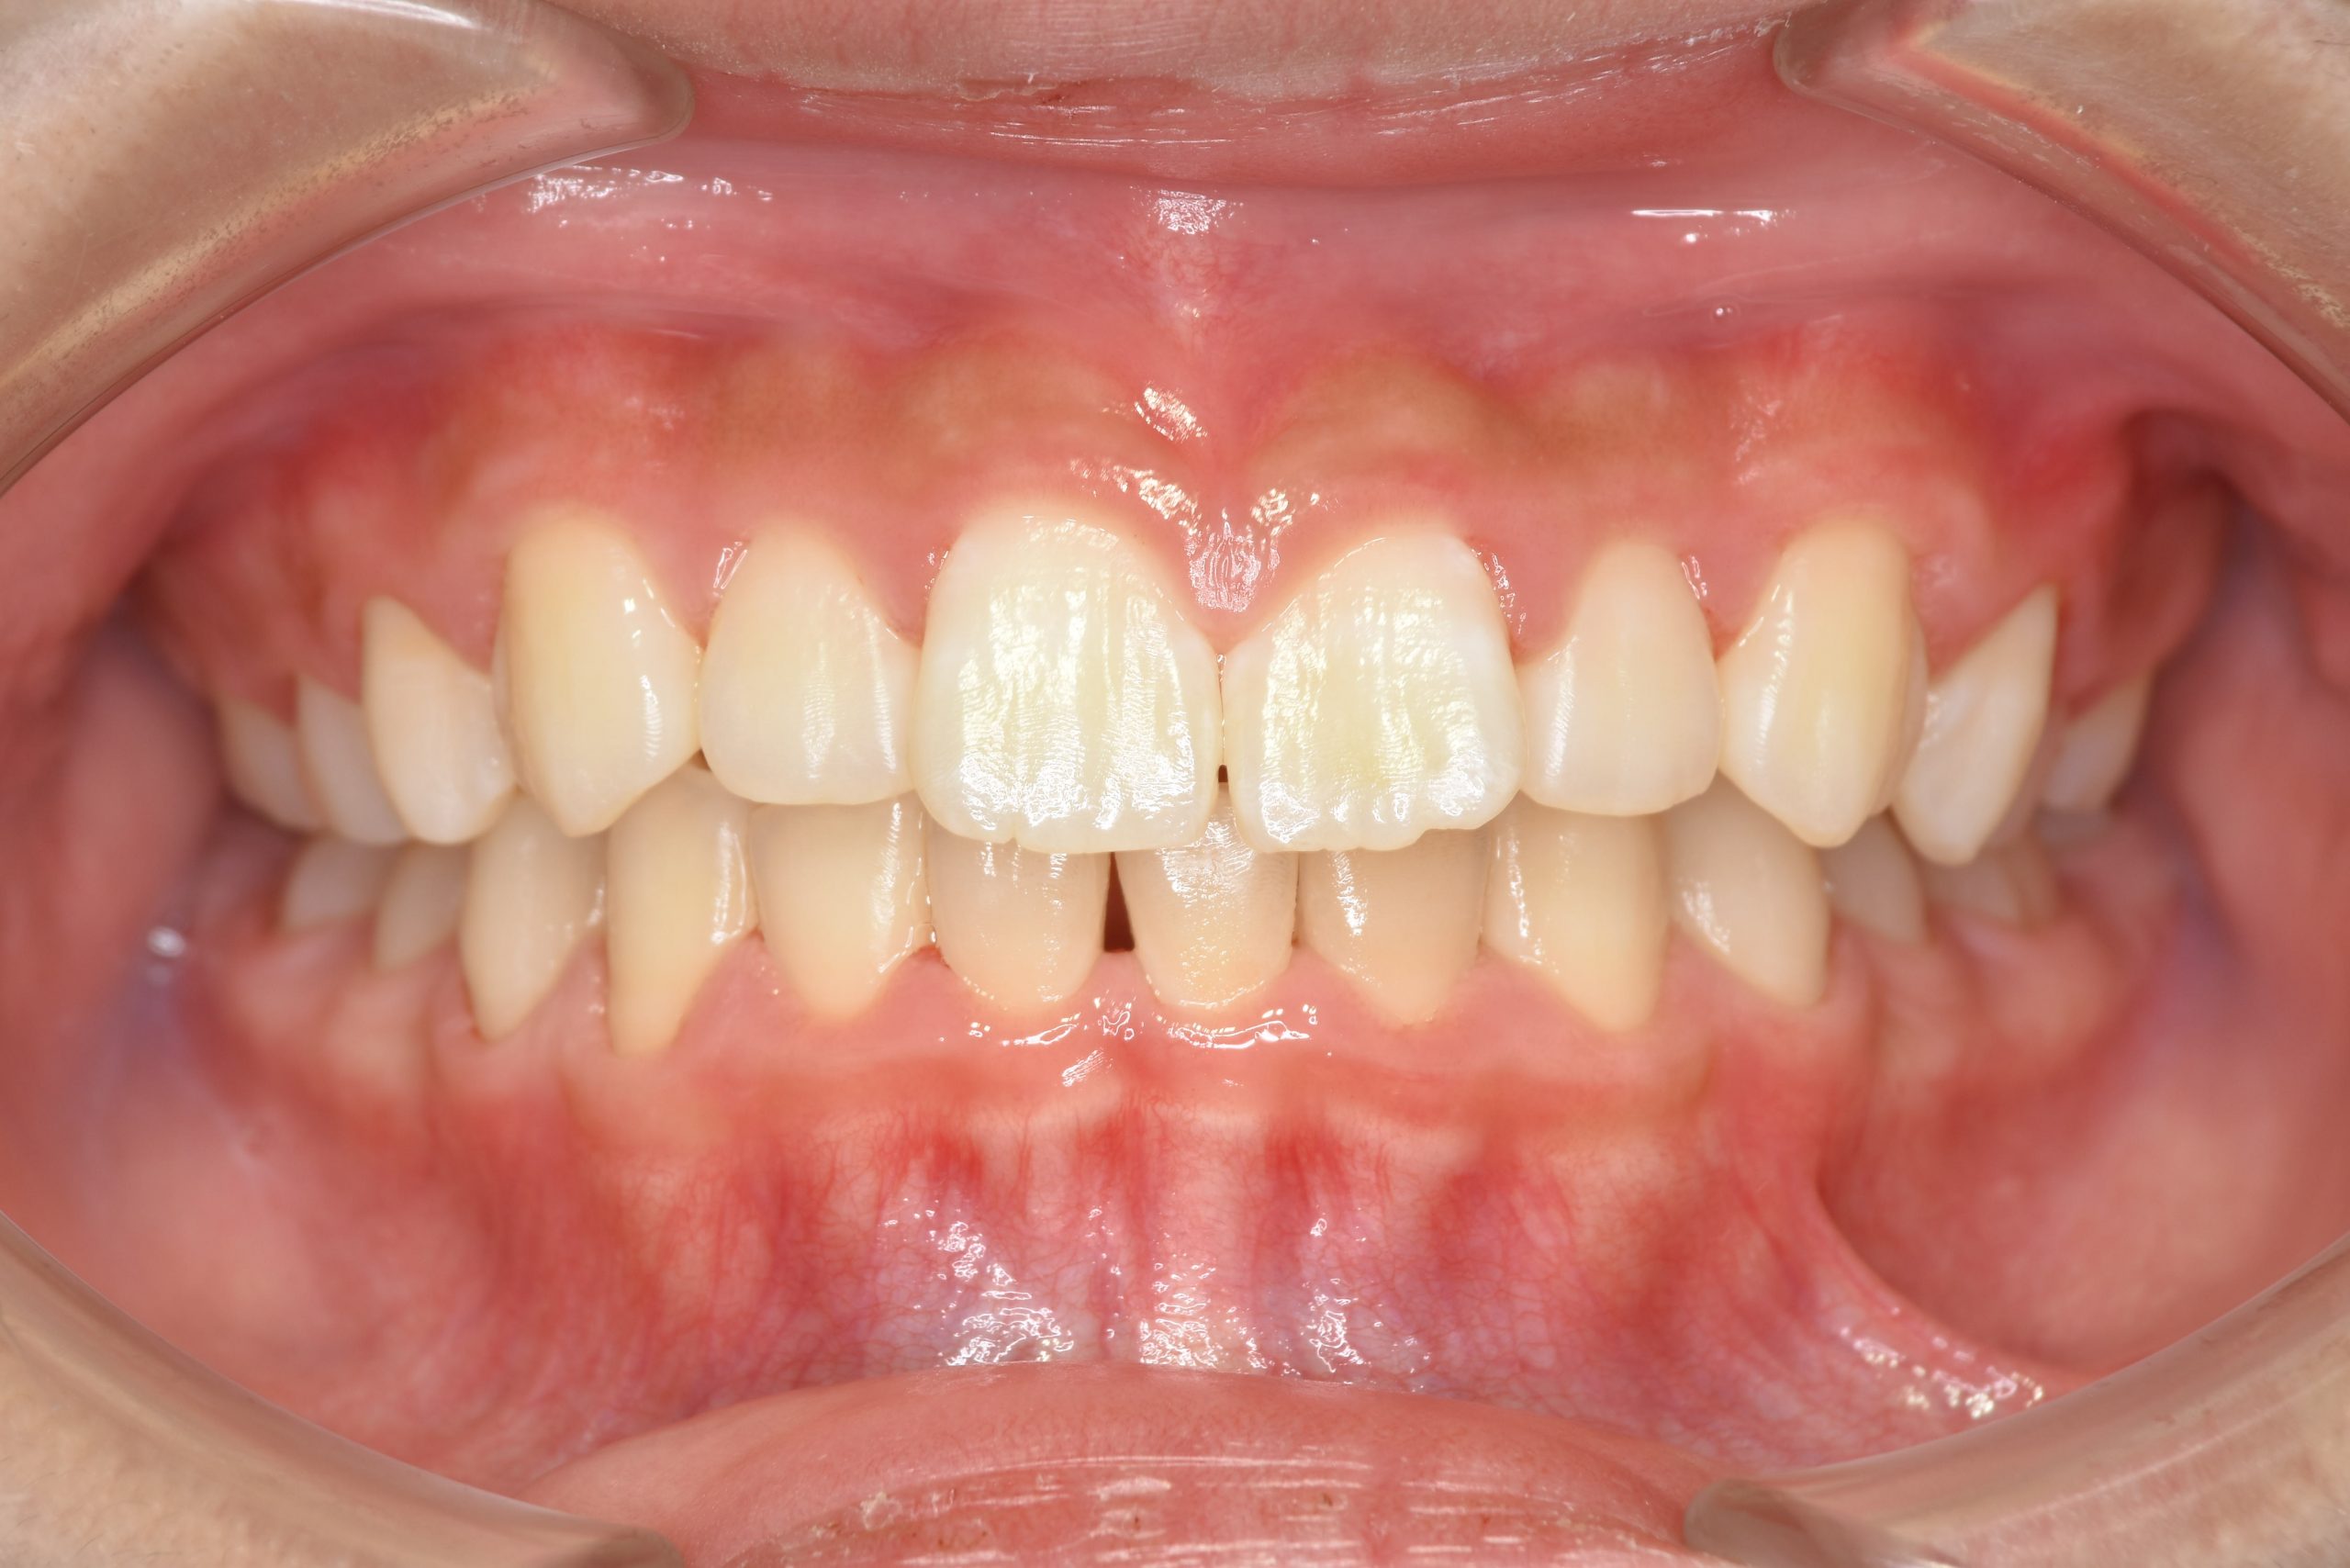

アフター

全顎ワイヤー矯正 症例_218